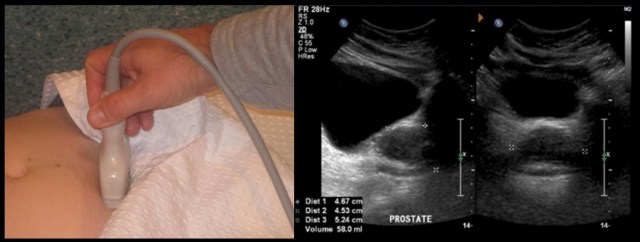

Esto va a depender del tipo de ecografía solicitada, para estudiar la próstata se pude realizar una ecografía abdominal o una a través del recto (transrectal). Las evaluaciones rutinarias de la próstata sólo utilizan la vía abdominal, dejando la vía rectal sólo para casos muy especiales y ante la sospecha de un cáncer de próstata.

La vía suprapúbica se ha mostrado eser tan fiable como la transrectal para la determinación del volumen, con la ventaja de ser menos laboriosa, mejor tolerada y tener una amplia difusión.

En este post sólo trataremos la ecografía abdominal.

Lo que calculamos con la ayuda de la ecografía es el volumen prostático, y para ello se realiza la toma de medidas longitudinal, antero posterior y transversal.